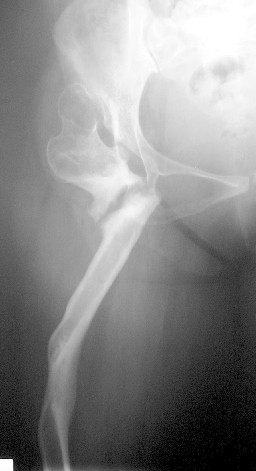

A 30-year-old female patient, presented with pain and limping post hip surgery and lengthening using Ilizarov technique 2 years duration.She said she had only limping preop. now she has painful limping and she can't walk without using walking aid.

Her X-ray --> non-union at the osteotomy site,pelvic tilt,bowing of the femur.clinically painful mobile pseudoarthrosis, LLD =4CM. Could those colleagues using such type of osteotomy Ilizarov method give us the clues how to treat such problems?Does this type of osteotomy still practiced by the group?Dr.Freih Odeh Abu Hassan,M.D(Orth.), F.R.C.S(Eng.), F.R.C.S.(Tr.&Orth.),Asst.Professor of Orthopedics Surgery,Jordan University - Amman.

Это вариант лечения по Илизарову при врожденном вывихе бедра у взрослых. Основан на методе Шанца (создание упора под впадину - вот как раз где не срослось), дополненный удлинением дистально с восстановлением механической оси бедра.